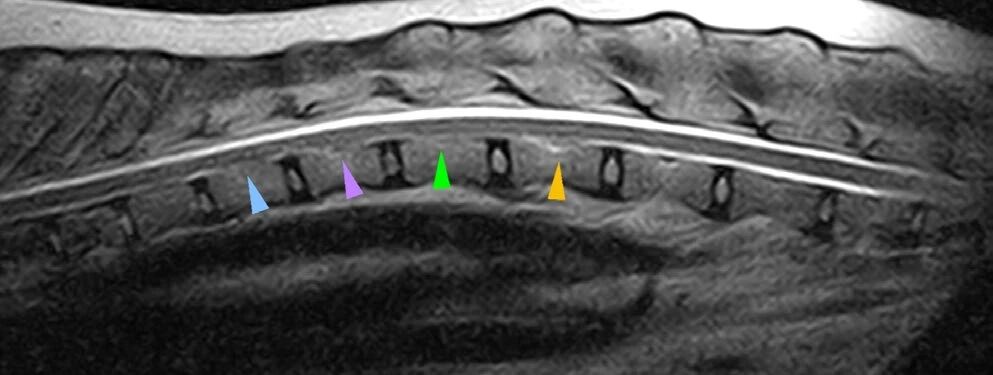

尸检脑部MRI未显示其他异常。脊髓显示T11-L2腹侧硬膜外间隙缩小,该区域中央管轻度扩大(下图)。

↑ 矢状面T2加权MRI显示脊髓(胸腰段)在Th11-L2区域的腹侧硬膜外空间减小(三角)以及该区域中央管轻度扩张。

↑ 横断面T1加权MRI显示第一腰椎的腹侧硬膜外空间减小(箭头),与该空间的背侧部分(三角)相比。